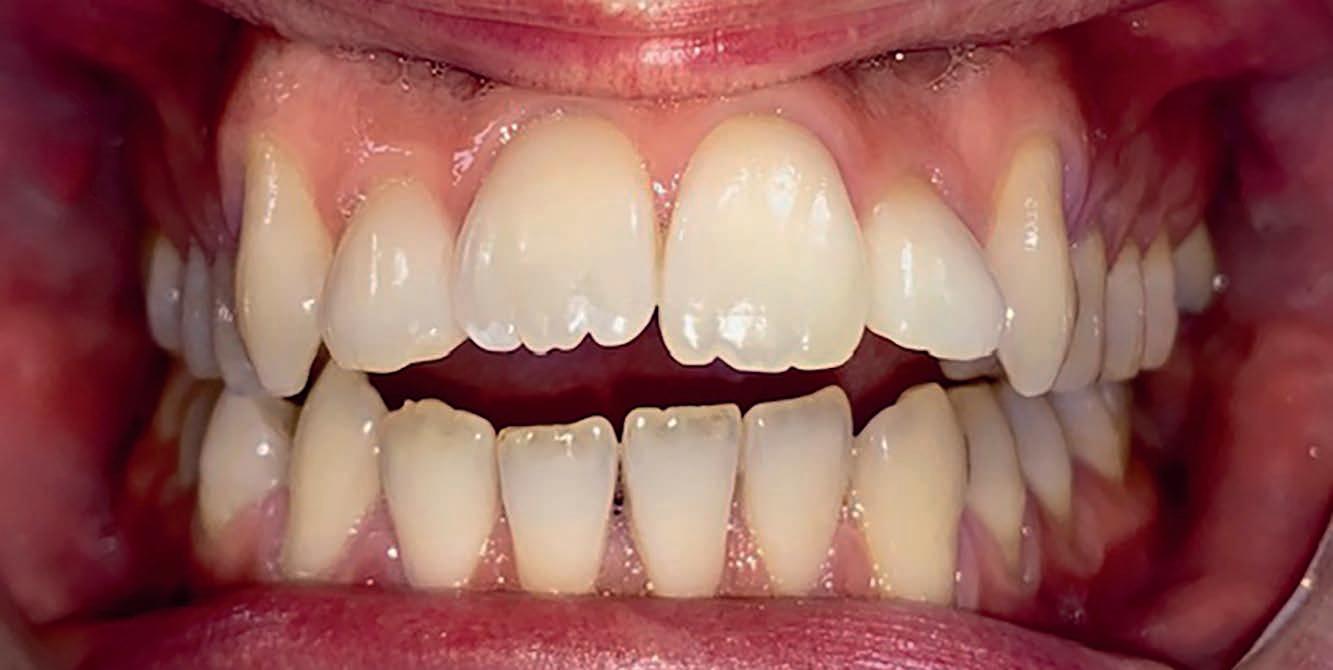

Casus: uit de Praktijk Sole & Jalissa.

Eén overbeet, twee gezichten

Sole en Jalissa kwamen op jonge leeftijd bij ons in de praktijk. Op het eerste gezicht leken hun gebitten totaal verschillend, maar achter de lach ging dezelfde afwijking schuil: een overbeet van 9–10 mm en versmalde tandbogen.

Bij Jalissa was de Klasse II-relatie direct zichtbaar: de bovenkaak stond duidelijk vóór de onderkaak en de lippen sloten moeilijk.

Bij Sole leek het minder opvallend. Haar bovenste snijtanden (11/21) stonden namelijk naar binnen gekanteld (Klasse II Divisie 2), waardoor de overbeet gecamoufleerd werd – maar de kaakrelatie was identiek.

Dit soort casussen laten zien waarom het belangrijk is om verder te kijken dan alleen de zichtbare tandstanden. Wat aan de buitenkant mild lijkt, kan functioneel en skeletaal net zo ernstig zijn.

Behandeling – starten met de juiste basis

Beide meisjes begonnen met een Twinblock-beugel, een functioneel apparaat dat de groei van de onderkaak stimuleert en de overbeet corrigeert. Ze droegen deze 9 tot 12 maanden.

Deze fase zorgde voor:

• Voorwaartse groei en positionering van de onderkaak

• Verbetering van de lip- en profielbalans

• Ruimte in de kaakbogen door natuurlijke verbreding

• Voorbereiding op een voorspelbaar verloop met vaste apparatuur (slotjesbeugel)

Na deze fase kan de slotjesbeugels efficiënt starten.

Waarom timing belangrijk is

Wij adviseren om een Twinblock te starten rond eind groep 6 of begin groep 7. In deze periode:

• is de groeispurt optimaal te benutten,

• is de motivatie hoger (voor middelbare school),

• en kan een operatie of complexe behandeling op latere leeftijd vaak worden voorkomen.

Te laat starten – bijvoorbeeld in de brugklas – betekent meestal minder groei, minder motivatie en grotere behandeluitdagingen.

Overbeet: 9 - 10 mm bij beide

Kaakrelatie: Klasse II (Jalissa)

Klasse II Div. 2 (Sole, 11/21 retrogekanteld)

Tandbogen: Versmald

Eerste behandeling: Twinblock, 9 - 12 maanden

Doel: Kaakrelatie corrigeren, profiel

verbeteren, ruimte creëren

Resultaat: Zachter profiel, betere balans, goede basis voor slotjesbeugel